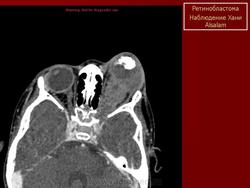

Наиболее характерный признак: внутриорбитальное объемное образование, содержащее обызвествления. Солидное образование сетчатки с центральной локализацией в задней части глазного яблока. Типично умеренное или интенсивное накопление КВ. Часто сочетается с неспецифической отслойкой сетчатки.

КТ-семиотика

Ретинобластома имеет вид мягкотканного объемного образования с наличием типичных точечных обызвествлений (менее 90%).

По данным КТ выделяют 3 степени роста ретинобластомы.

I степень – опухоль располагается внутри глазного яблока, часто содержит мелкие кальцинаты, плотность не увеличивается после контрастирования;

II степень – в процесс вовлечены ретроорбитальные ткани и зрительный нерв, края глазного яблока нечеткие, кальцинаты встречаются редко;

III степень – процесс выходит за пределы глазницы, опухоль хорошо конграстируется, кальцинаты не встречаются.

Однако такая динамика процесса встречается не всегда. В ряде случаев опухоль, видимая при офтальмоскопии, на томограммах не дифференцируется, а все глазное яблоко имеет значительно повышенную плотность, в 2-3 раза превышающую обычную, что, очевидно, объясняется изменением структуры всех сред глаз, на фоне которых выделить опухоль не удается

Участки повышенной плотности, выявляемые при ретинобластомах, не всегда обусловлены кальцинатами, в ряде случаев это мелкие кровоизлияния, которые в условиях КТ имеют высокую плотность